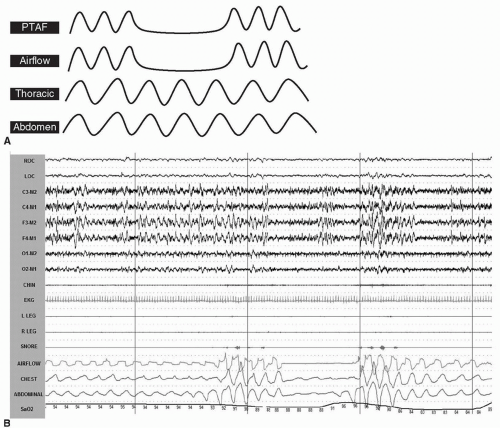

A central apnea (see Fig. 39-3A, B) is defined as cessation of airflow (drop in signal by ≥90% of the preevent baseline using an oronasal thermal airflow sensor) with absent respiratory effort throughout the entire event.

The duration of the event is greater than or equal to 10 seconds.

![]() Figure 39-3 A, B: Central apnea. In this example, the airflow as well as the respiratory effort is completely absent. PTAF, pressure transducer airflow. |